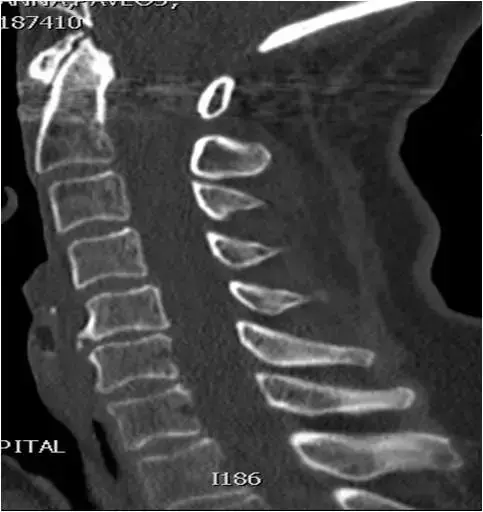

图17:颈椎CT扫描。矢状位重建。C5相对于C4椎骨的轻度后移位。C5-C6关节间隙狭窄,轻度终板硬化和同一水平的小前骨赘。像。